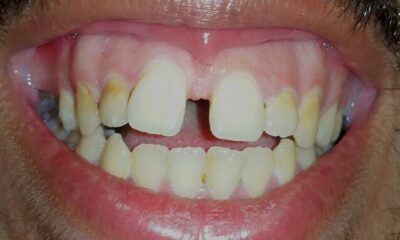

A narrow maxillary arch may not provide enough room for the teeth, predisposing to crowding and malocclusion. This can lead to compensatory strain patterns throughout the body (Adhikari et al, 2011). The problem becomes more pronounced when accompanied by a reverse swallow pattern—an anterior tongue thrust—where the tongue pushes forward against the front teeth while the cheeks and lips draw inward through overactivity of the buccinator, orbicularis oris and mentalis muscles.

This infantile swallow pattern originates as a primitive reflex supporting breastfeeding but may fail to integrate into a mature swallow, especially if breastfeeding is not initiated or ends too early. In a normal adult swallow, the tongue moves upward in a wave-like motion against the palate while the facial muscles remain relaxed. In contrast, with a reverse swallow, the tongue pushes forward into the front teeth, which over time can lead to an anterior open bite and increased postural tension.

Often accompanying this pattern, the tongue habitually rests on the lower teeth or between the arches, preventing normal tooth eruption and reducing vertical height. This can further disrupt occlusion and contribute to strain through the craniofacial and cervical regions. Malocclusion is commonly associated with imbalanced cervical, cranial and facial posture and may contribute to temporomandibular joint (TMJ) dysfunction, neck pain and headaches. Ideally, after every swallow the teeth should lightly touch. However, when interferences exist during this contact phase, they can compound postural problems.

Anterior Open Bite

Tongue Thrust